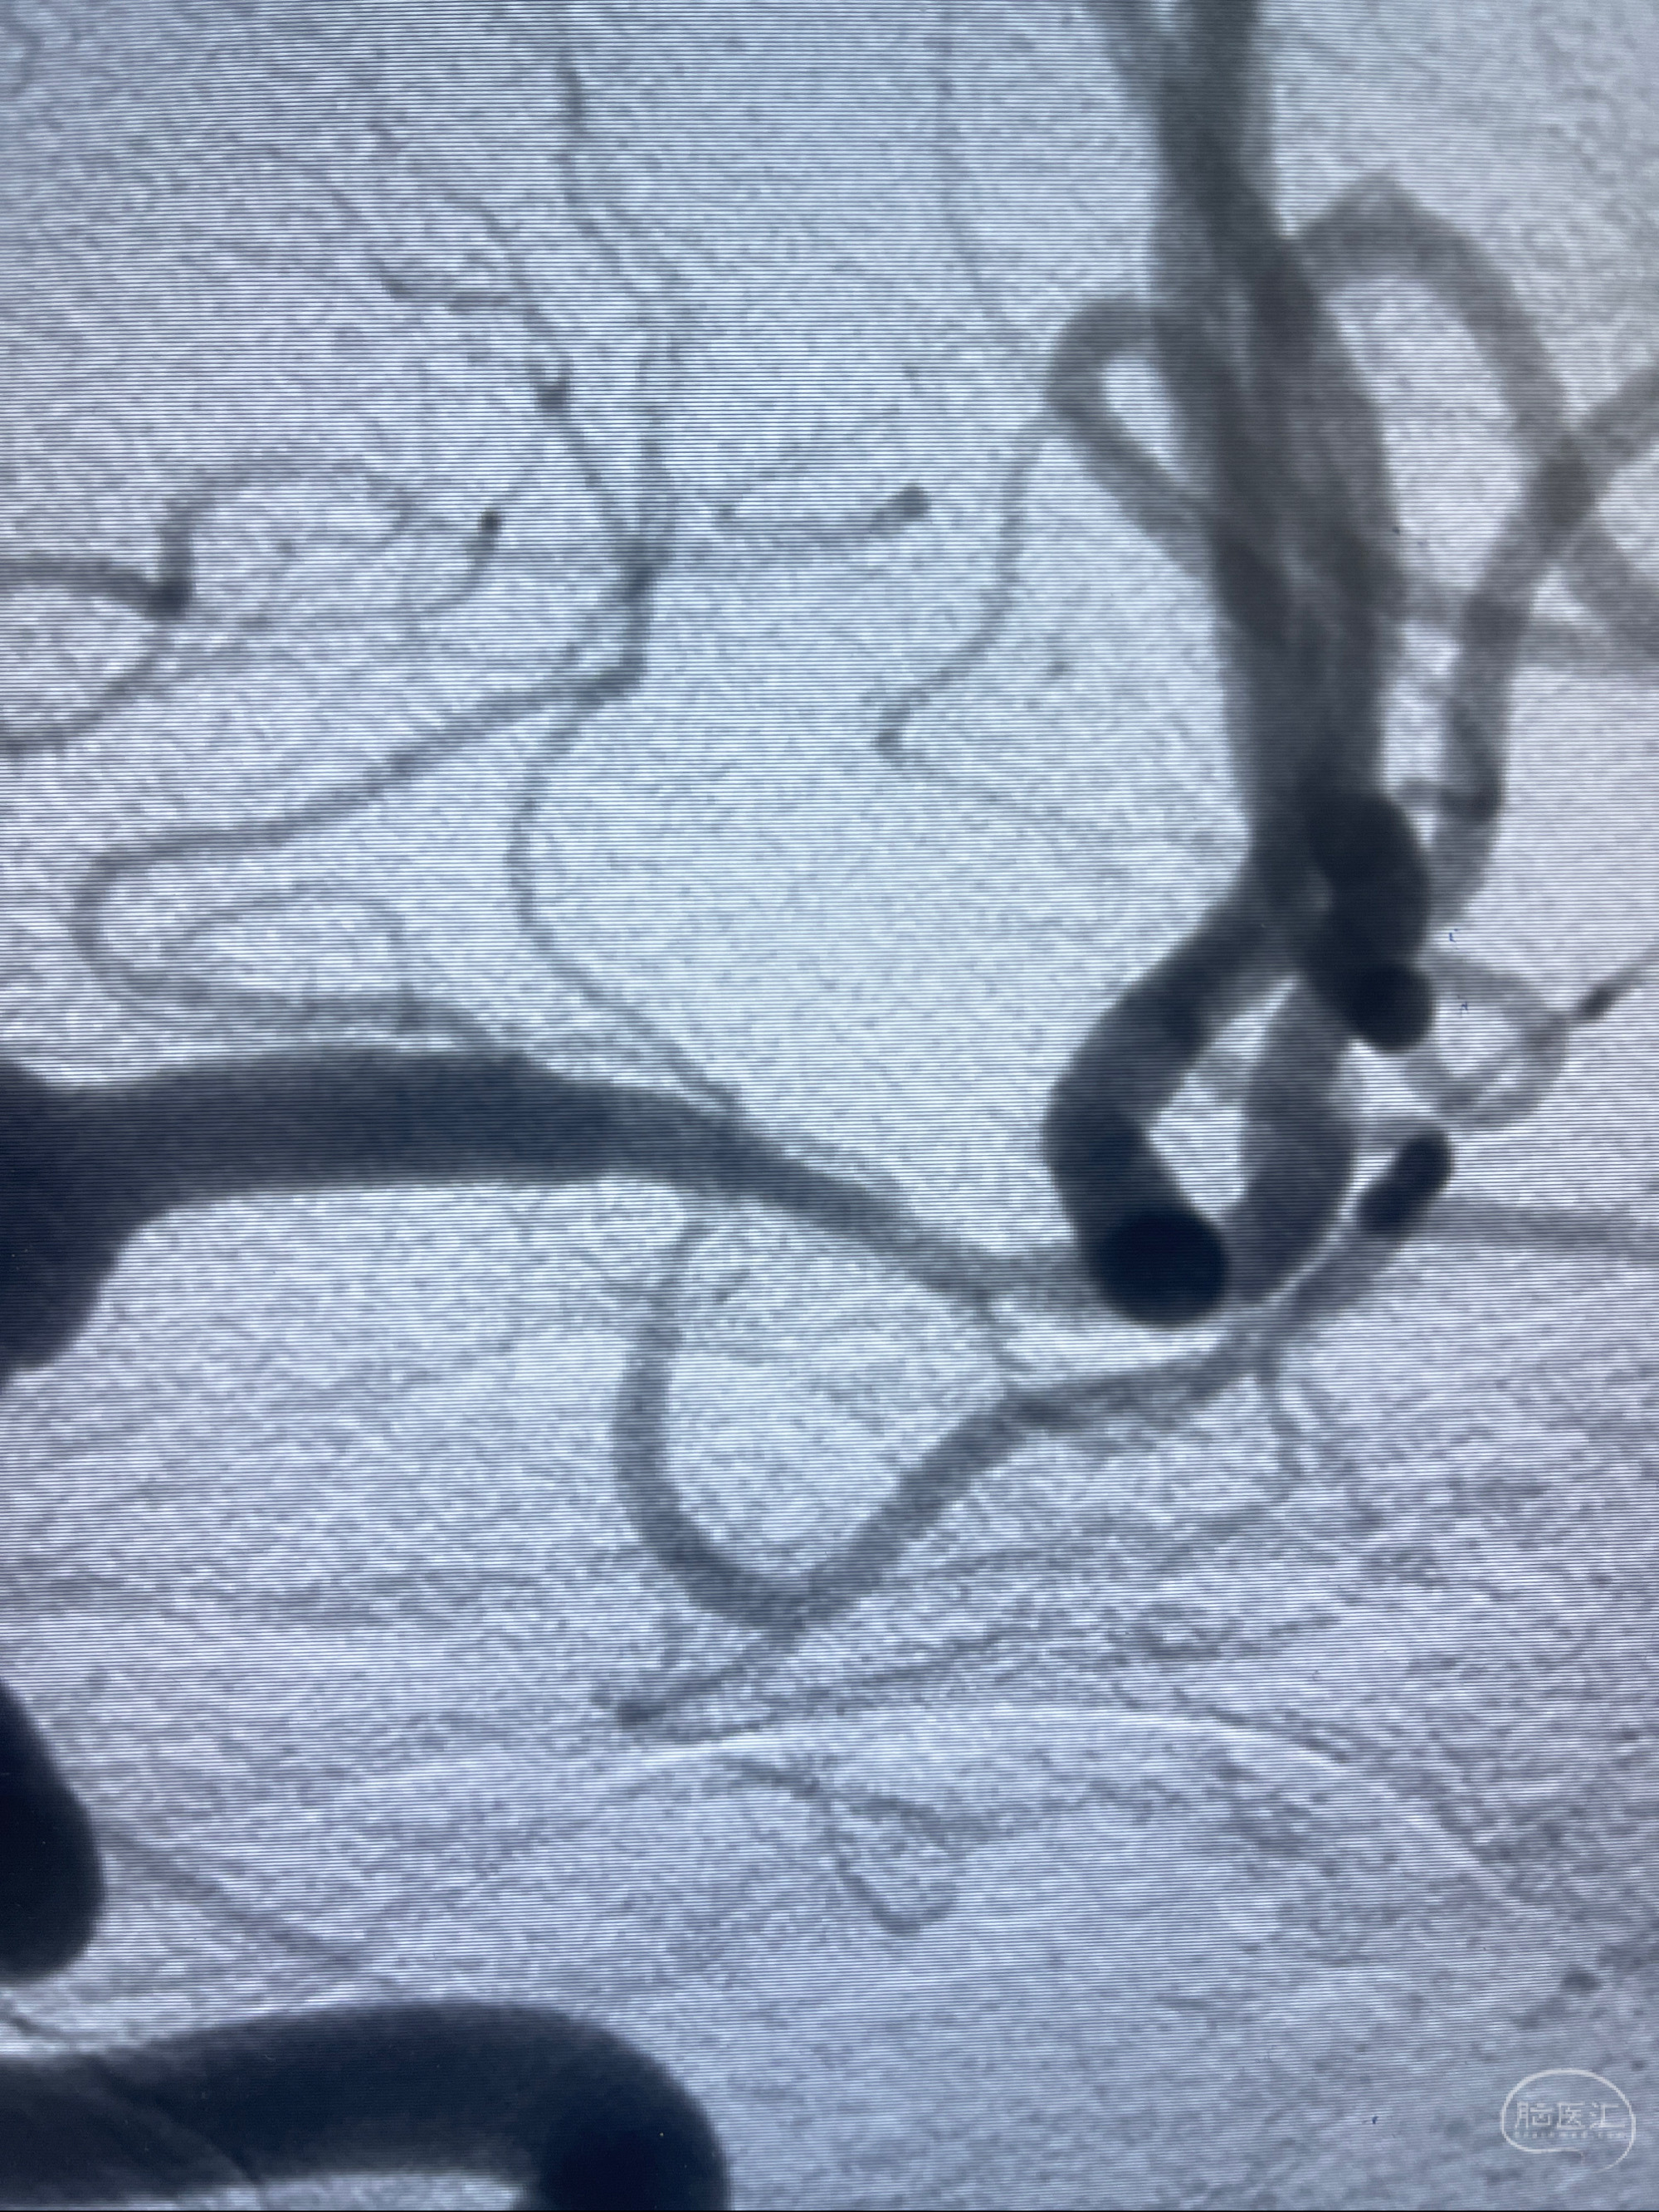

2023-02-15DSA